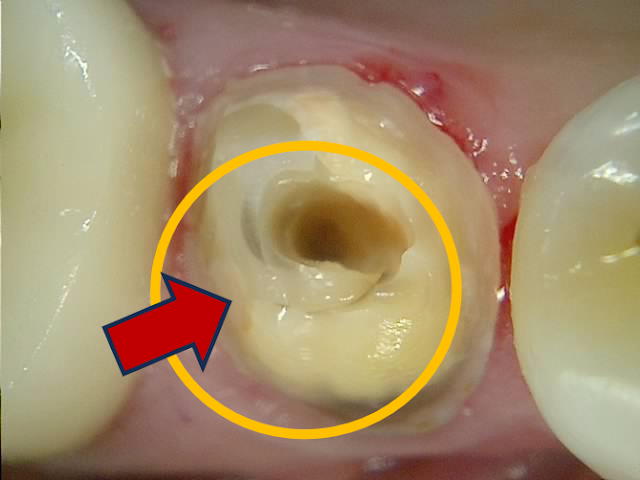

크라운을 제거하고, 신경관 입구에 접근하려는데.. 시작부터 숨이 턱 막힌다.

어디가 포스트고 어디가 치아인가...

뿌리염증이 생긴 치아의 재신경치료를 위해 파이버 포스트 제거 시작

조심조심 레진 포스트로 추정되는 부분을 깎아내면서 아래로 접근.. 더 들어가도 구별이 안 된다.

재신경치료를 위해 파이버 포스트 제거 중 확인하는 사진

- 입속에서 보면 치아와 전혀 구별이 안 된다.

치아와 구별이 되지 않는 파이버 포스트

- 치아에 난 작은 구멍을 통해, 저 치아색의 기둥만 삭제해야 하니.....